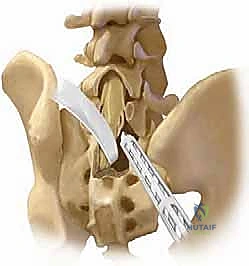

2. الدمج الخلفي الجانبي (Posterolateral Fusion - PLF)

بعد تحرير الأعصاب، يجب تثبيت العمود الفقري. في تقنية الدمج الخلفي الجانبي، يتم وضع مسامير من التيتانيوم (Pedicle Screws) في جذور الفقرات، وتوصيلها بقضبان معدنية قوية. ثم يتم وضع طعوم عظمية (Bone Grafts) - تؤخذ عادة من عظام الحوض للمريض أو من بنك العظام - على الأجزاء الجانبية للفقرات (Transverse Processes). بمرور الأشهر، ينمو العظم الجديد ليلحم الفقرات معاً ككتلة عظمية واحدة صلبة، مما يمنع أي حركة غير طبيعية.

3. دمج الفقرات بين الأجسام الفقرية (PLIF / TLIF)

في حالات الانزلاق عالي الدرجة، غالباً ما يتطلب الأمر دعماً إضافياً من الأمام (بين أجسام الفقرات). هنا يتألق الدكتور هطيف باستخدام تقنيات (PLIF - Posterior Lumbar Interbody Fusion) أو (TLIF - Transforaminal Lumbar Interbody Fusion).

في هذه التقنية، يتم استئصال القرص الغضروفي التالف بالكامل، ووضع قفص داعم (Cage) مصنوع من مادة الـ PEEK أو التيتانيوم، ومملوء بالطعوم العظمية، في مكان الغضروف. هذا الإجراء يعيد الارتفاع الطبيعي للفقرات، ويفتح مسارات الأعصاب بشكل ممتاز، ويوفر نسبة نجاح للدمج العظمي تقارب 100% لأنه يضع العظم في منطقة تتحمل ضغطاً ميكانيكياً عالياً مما يحفز نمو العظام.